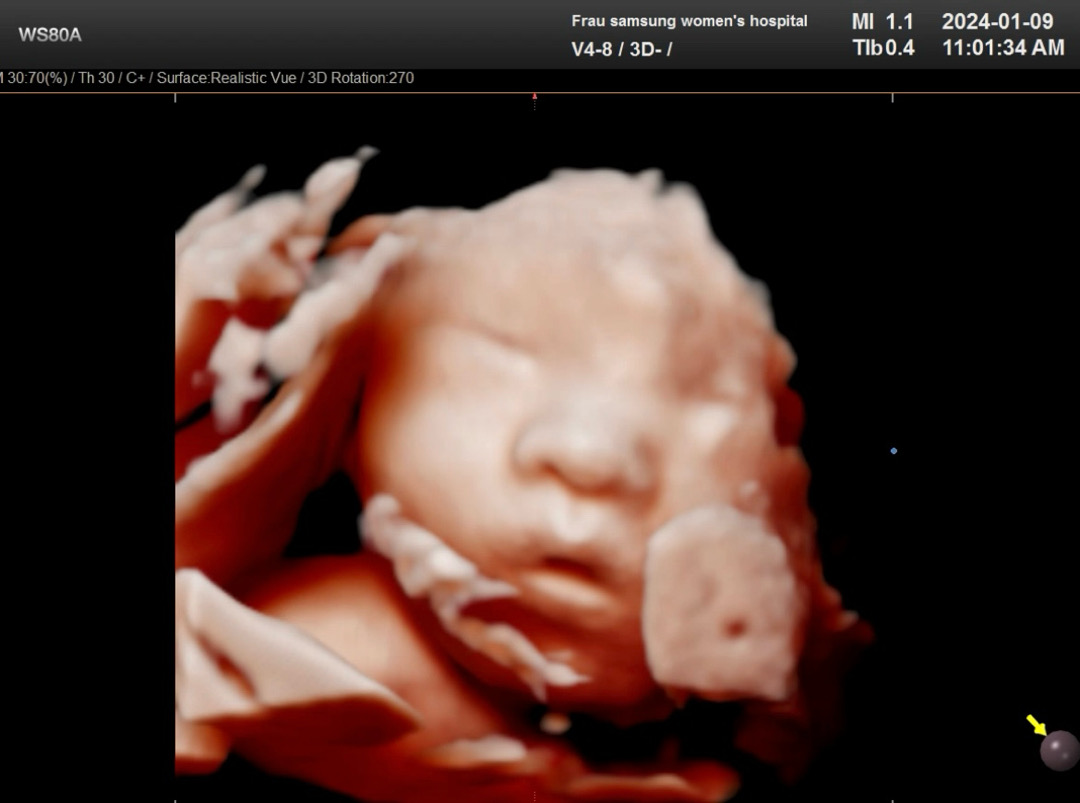

역아돌리기+입초성공🫶

항상 역아여서 입초를 30주때까지 본적이 없었어요.. 담당쌤도 이젠 아기 돌려야된다면서 역아체조 열심히 하라고 하셔서 정기검진 2주 텀동안 공복이랑 자기전에 5분씩 했더니 돌리기 성공! 덕분에 32주만에 우리 만두 얼굴 보기 성공👶🥰 임당산모라 아기가 작진 않을까 했는데 (32주동안 +3키로)딱 주수에 맞게 잘 크고 있고 얼굴에 살 포동포동 붙은거 보고 안심했네요🫶 너무 귀여워요🥰🥰🥰🥰 다들 분만방법 정하셨나요? 다음정기검진까지 정해오라 하셨는데 조언 부탁드립니다 :)